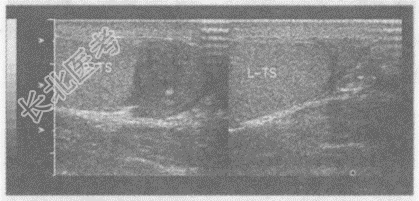

超声综合描述:右侧睾丸形态、大小正常, 内回声均匀。右侧附睾尾回声减低,范围: 4.1cm×4.3cm,内回声不均, CDFI:内可见丰富动静脉血流信号, PW:以动脉频谱为主, V

17.0cm/s。见下图及彩图46。